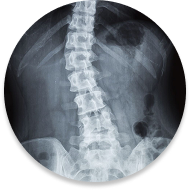

Scoliosis

Scoliosis is a sideways curvature of the spine that may develop duringgrowth or later in life. It can cause asymmetry, stiffness, fatigue, or discomfort,and management focuses on posture, movement, and strength.